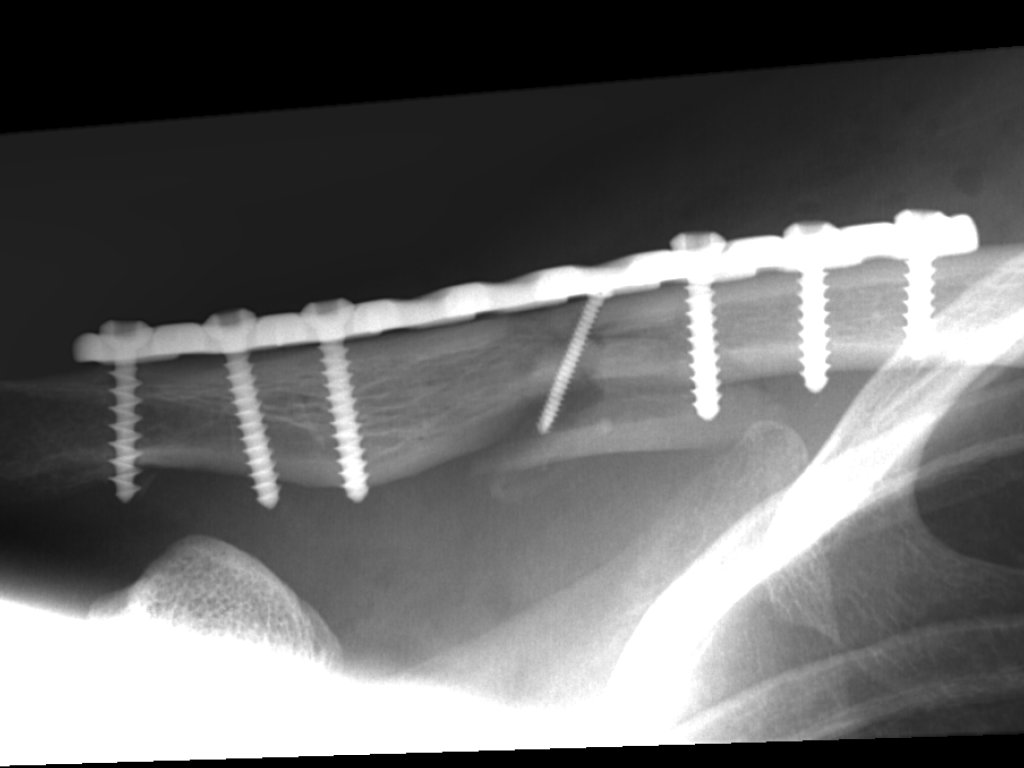

Clavicula-Fraktur (23./25. Juli/2. August 2007)